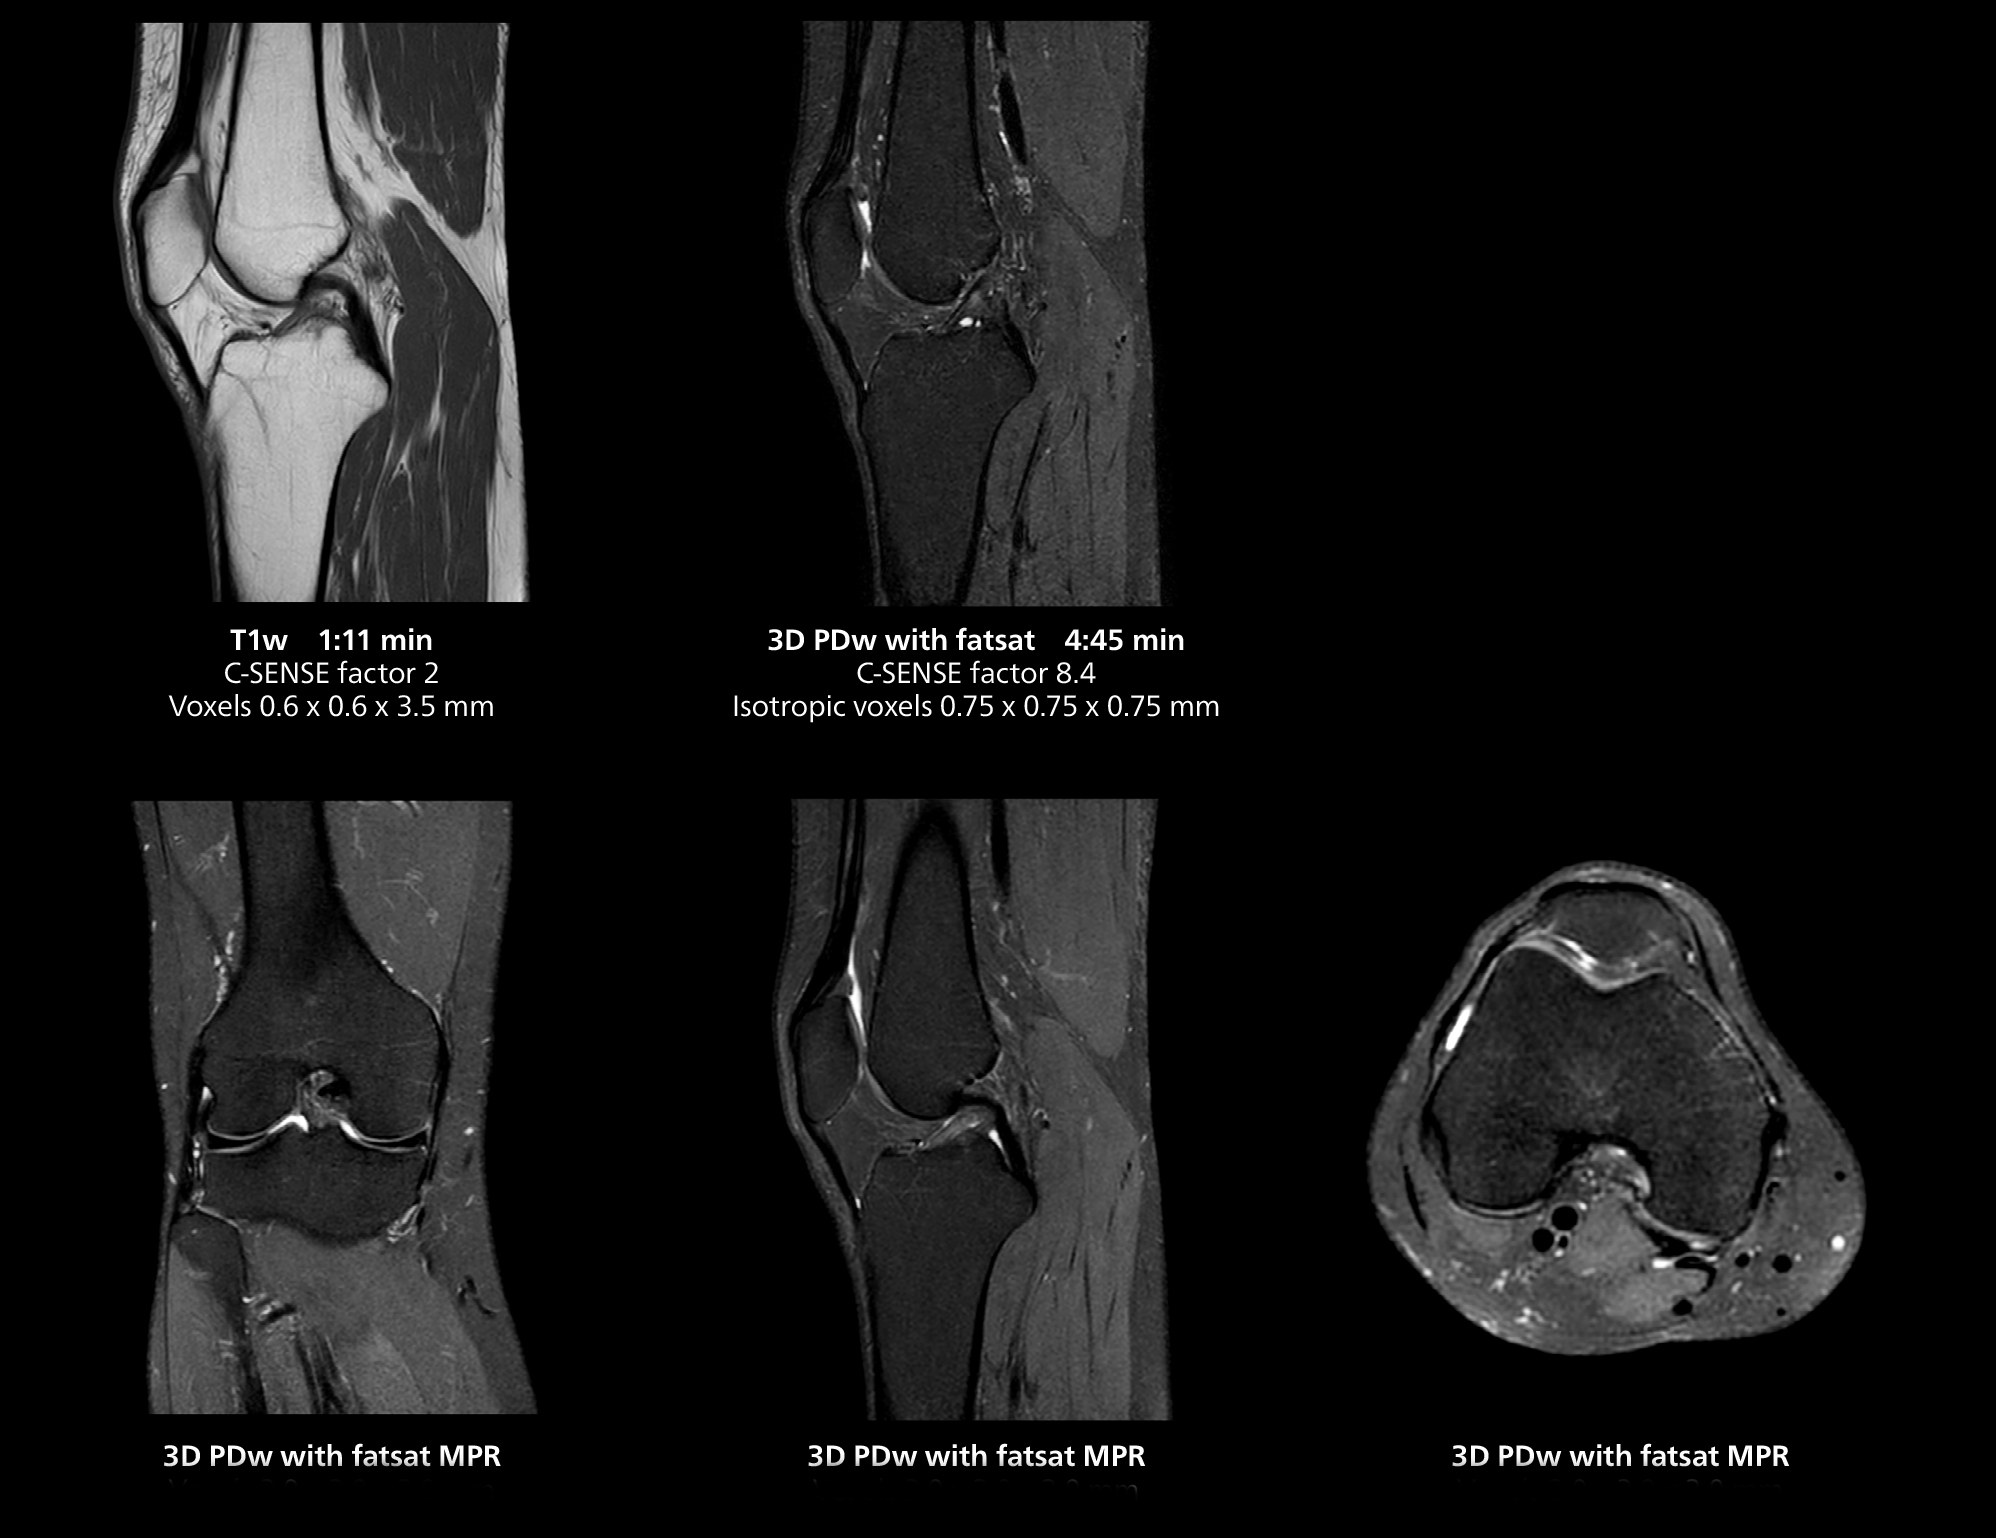

The isotropic high resolution 3D sequence in this MRI case allows for reformatting to obtain other orientations with high quality. Acquired on the MR 5300 system.

“We have more speed in 3D sequences,” Dr. Gellée states. “With Compressed SENSE, we can replace two or three 2D scans withone high-quality 3D scan. High quality additional orientations are then obtained by post-processing of the 3D data set, thus saving scanning time.”

According to Dr. Gellée, the hospital conducts an average of four studies each hour, totaling about 40-45 patients per day on their MR 5300. Studies are read by approximately 50 radiologists in the Bordeaux area. Dr. Gellée is especially satisfied with the image quality of the MR system. "I obtain higher image contrast and more anatomical precision than I was used to,” she says. “When I am able to choose, I request that studies be done on this system, because I get better anatomical image quality. For example, in the knees, I can get great images of the meniscus. To me, it looks as pretty as 3T.”